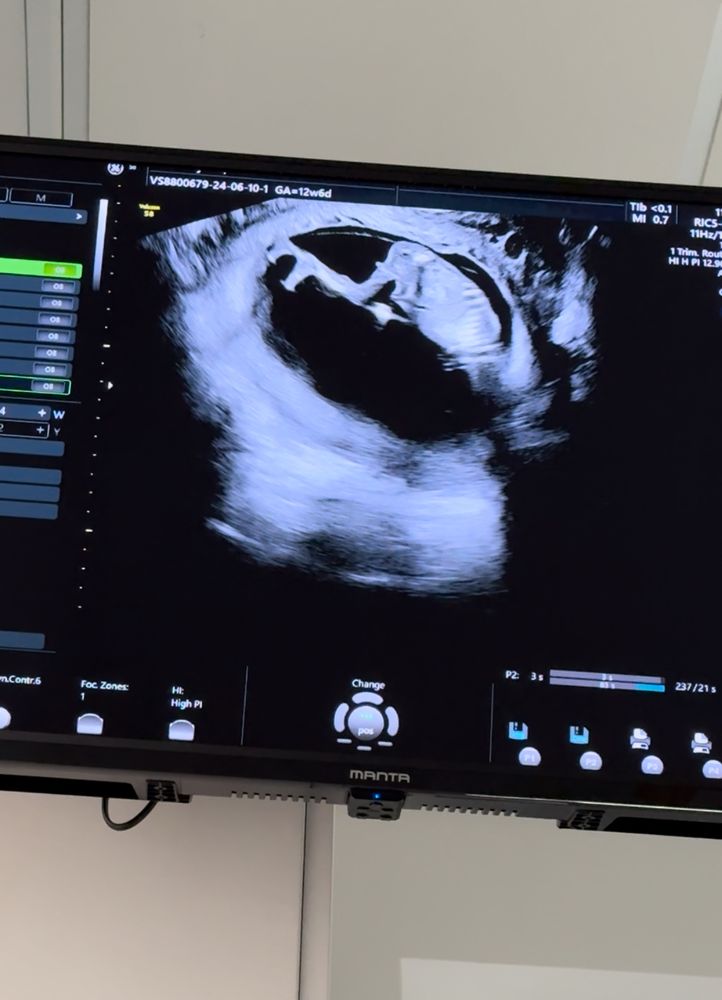

Пол малыша в 12,6 недель 🤔

Тут не видно полового бугорка=) ждите кровь

По бугорку девочка

Это девочка